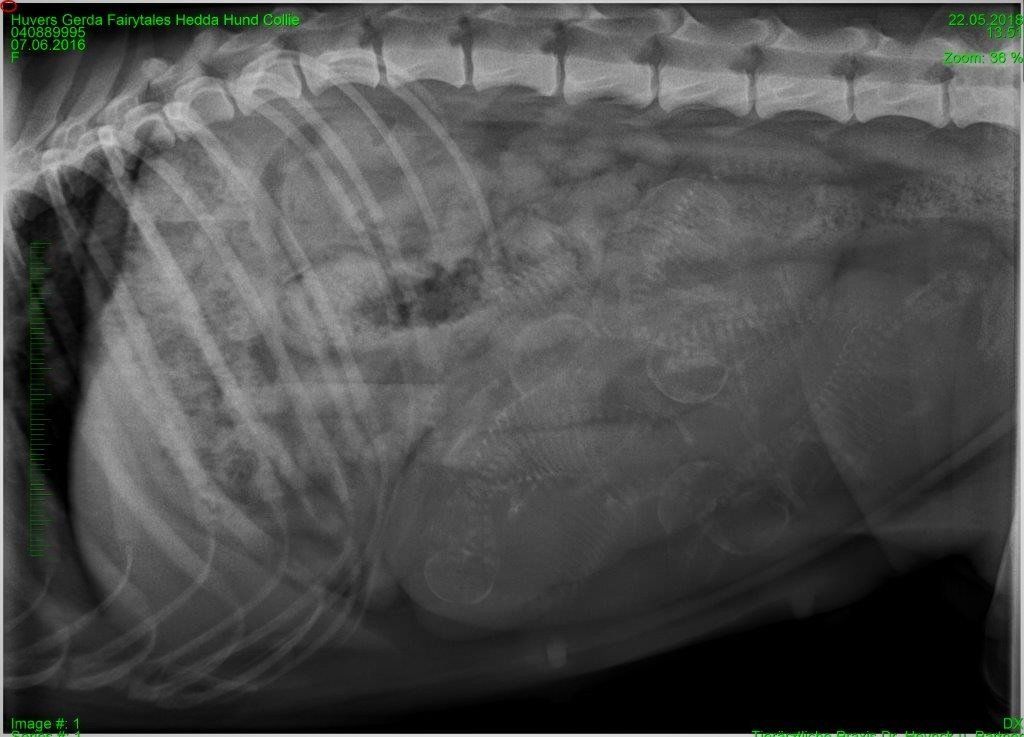

Wir waren heute beim Tierarzt zum Röntgen.

Hedda hat 6 Babys im Bauch, freu :-)

Natürlich haben wir sie dann auch gleich nochmal gewogen, oh je, Hedda bringt 29.8 kg auf die Waage.

Der Bauchumpfang misst jetzt 82 cm. Bin mal gespannt wie viel noch kommt , immerhin hat sie noch 1 Woche vor sich.